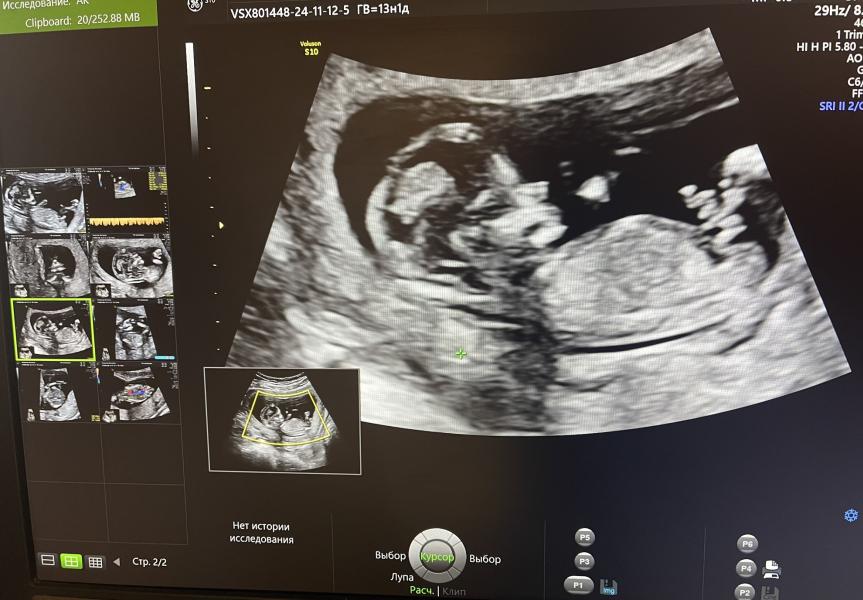

Первый скрининг 😍🐣

Делала очень хороший врач в ГКБ 29

Мой маленький очень активный, ручками и ножками машет. Отталкивается. Еле поймали, чтобы все измерить 😀

Сказали, что вроде мальчик. потом еще посмотрела и говорит «да точно мальчик, даже мошонку видно» 💙